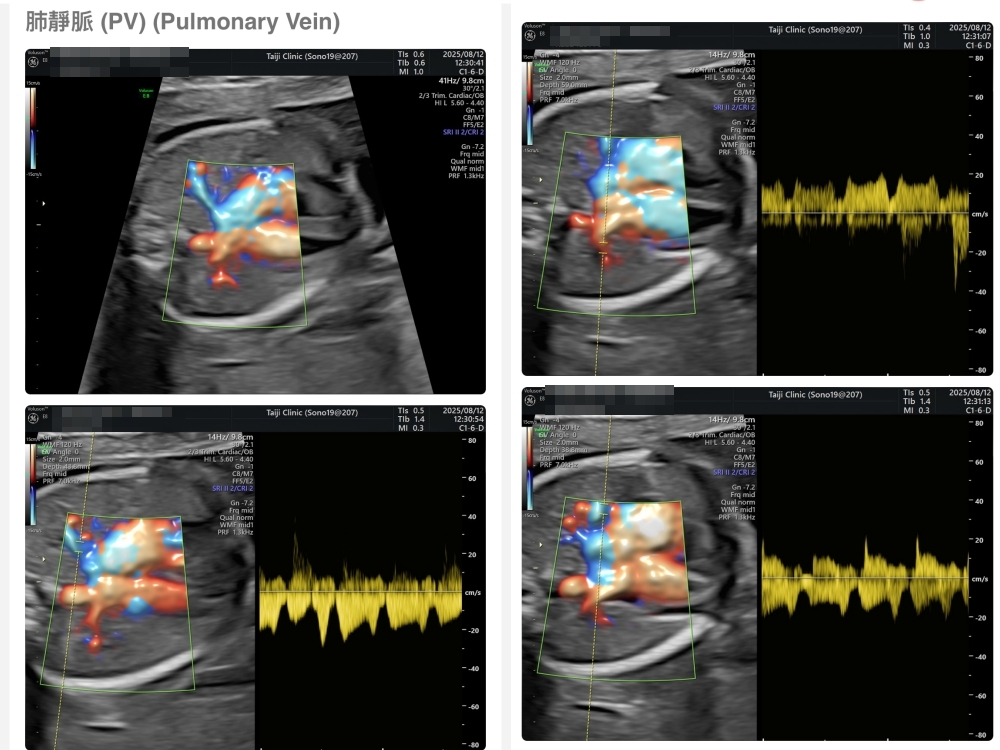

【台兒|高層次超音波|檢查結果】

▲離開診所後會收到MAIL,我們14:05離開,大約是16:45收到mail,裡面會有滿滿的超音波照片,紀錄的很詳細!也會提供紙本的報告,可以給日後產檢的醫師做參考👌